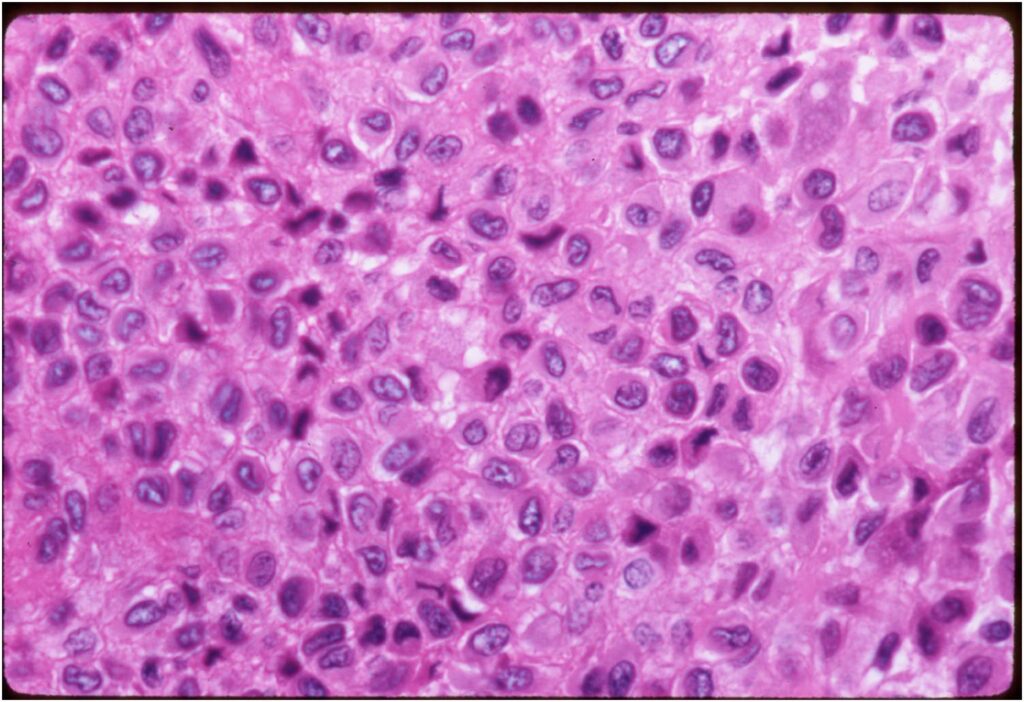

Microscopic Pathology

- Variable appearance depending on percentage of cells, necrosis, cartilage matrix formation and ABC change

- The tumor is composed of chondroblasts that have a distinct, thick cell membrane. The thick cell membrane gives it a “Chicken Wire Fence Appearance,” especially when the cell membranes are calcified